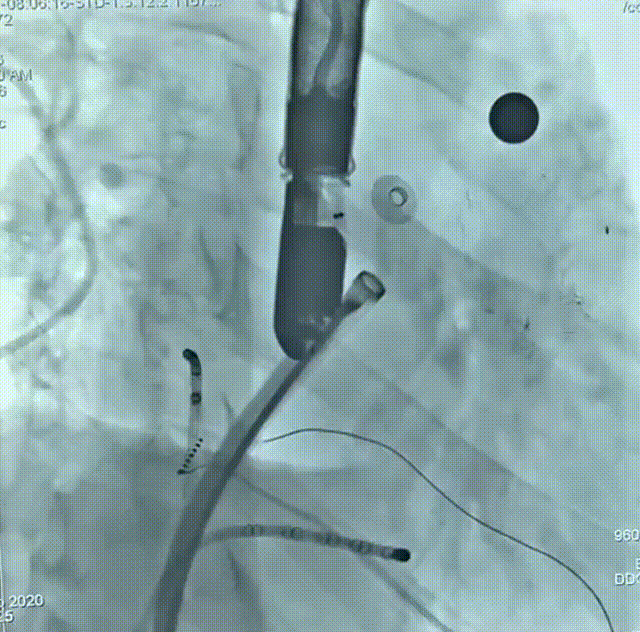

患者为51岁男性,因“反复心悸7-8年”入院,有明确的脑梗死病史,近4年内出现2次脑梗死,右侧肢体存在活动障碍后遗症,考虑由房颤相关血栓栓塞造成。术前动态心电图示心律不齐,房颤律,心脏彩超示左右房内径增大、左室收缩功能减低;房颤CHA?DS?-VASc评分4分、HAS-BLED评分4分,血栓栓塞及出血风险均较高;食道超声联合CT重建示左房及心耳内未见明显血栓形成,左心耳偏大。结合评估结果和患者及家属意愿,拟使用我国自主研发的Bio-Lefort生物可降解左心耳封堵器,行导管消融+左心耳封堵“一站式”手术。射频消融完成后实施左心耳封堵,术中牵拉试验提示封堵器稳定,符合释放原则,整个封堵器释放过程一气呵成,术后造影显示无残余分流,术后超声证实封堵器位置良好,封堵结果十分理想,顺利完成手术。

术后造影